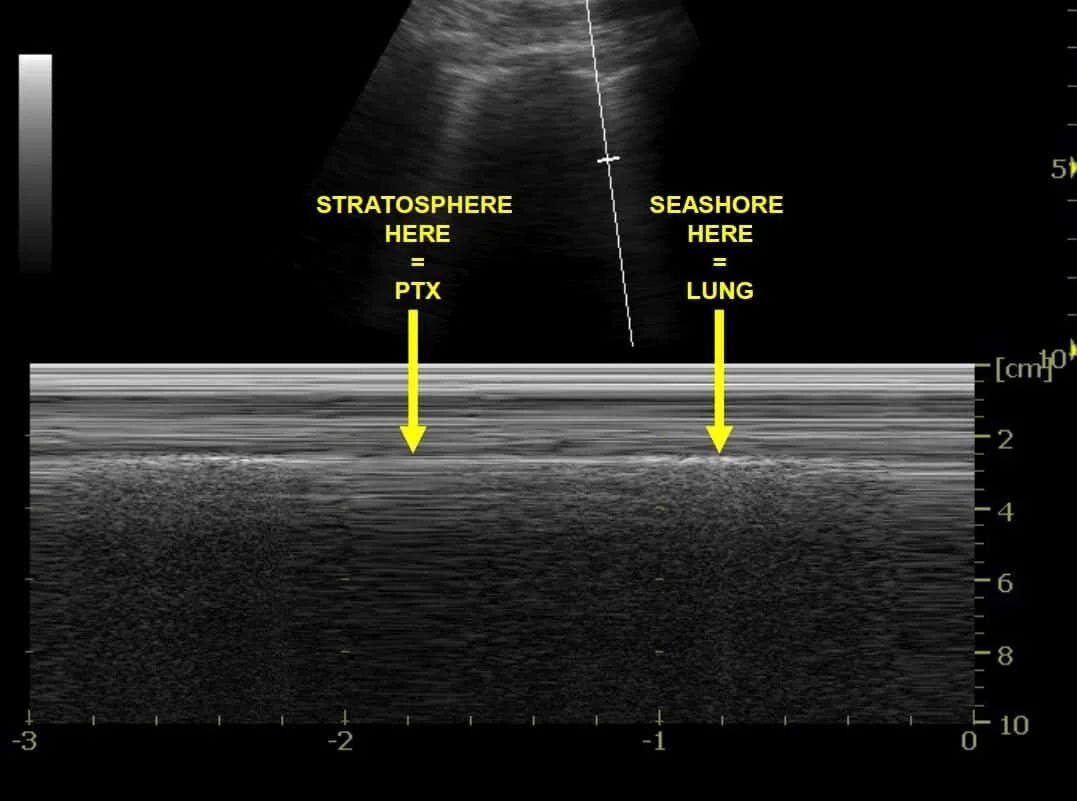

●     With M-mode, properly inflated lung is confirmed with the “seashore sign,” where pleural movement is seen as the grains of sand, and the more superficial subcutaneous tissue anterior to the pleura is the water.

●     With M-mode, pneumothorax is suggested by “barcode/stratosphere sign,” which shows absence of movement both superficial and deep to the pleural line.

Figure 1 & 2: Lung point on B-mode (left); Lung point on M-mode (right).